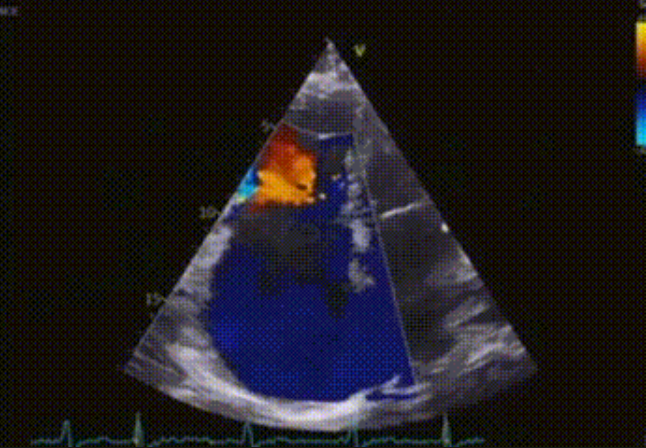

術(shù)前心臟超聲提示:極重度三尖瓣返流,右房容積明顯增大,三尖瓣瓣環(huán)顯著擴(kuò)張。

術(shù)后心臟超聲提示:LuX-Valve Plus植入后,三尖瓣瓣環(huán)處可見人工瓣膜回聲,未見返流,人工瓣膜穩(wěn)定,瓣葉開閉良好,連續(xù)多普勒估測三尖瓣平均跨瓣壓差僅為1mmHg。